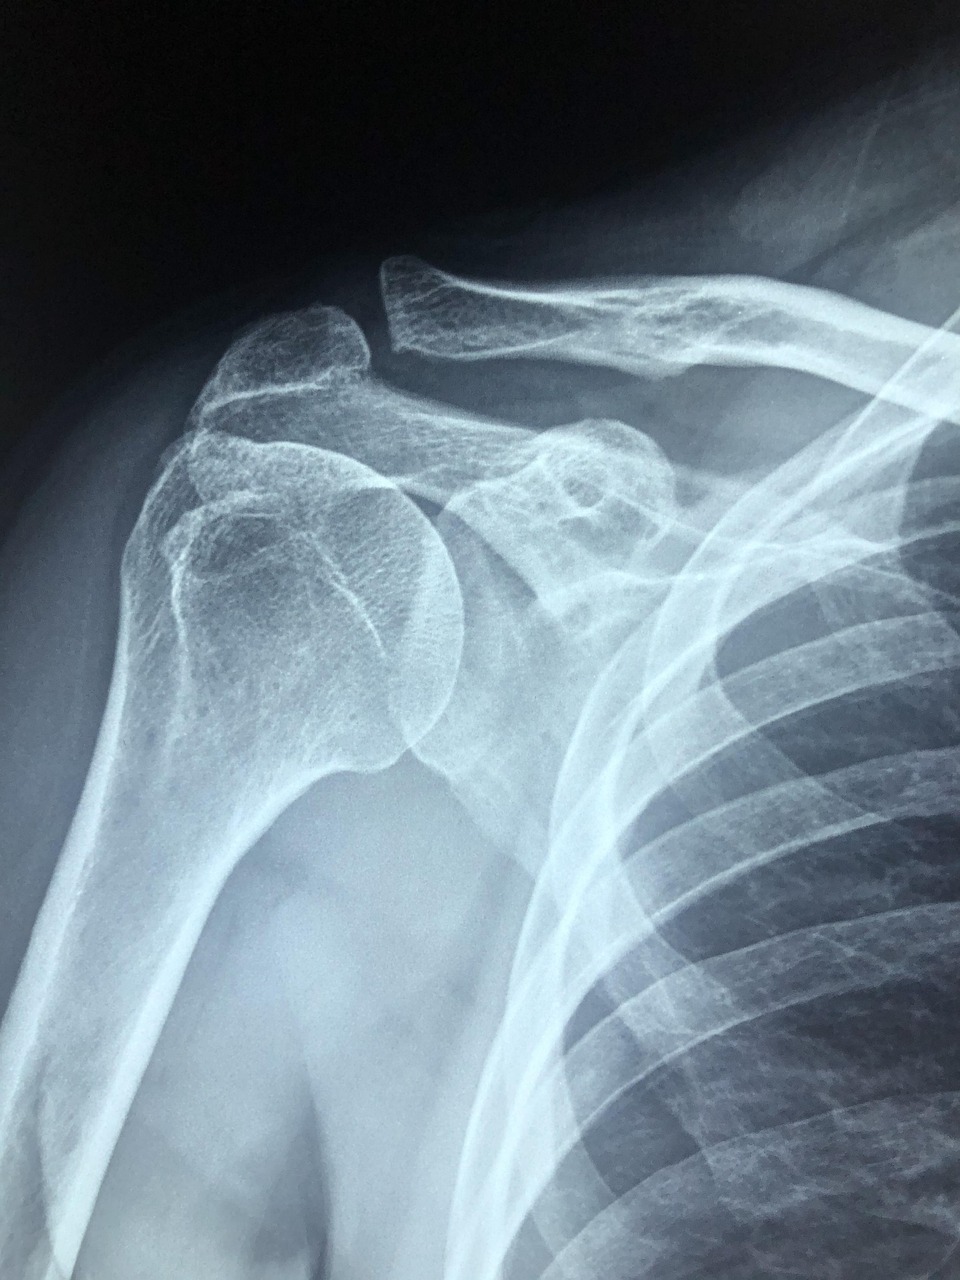

어깨 석회화 건염은 어깨 힘줄(회전근개) 속에 칼슘이 침착되어

석회처럼 단단한 덩어리가 만들어지는 상태를 말합니다.

이 석회가 힘줄을 자극하면서 통증과 염증이 생기게 됩니다.